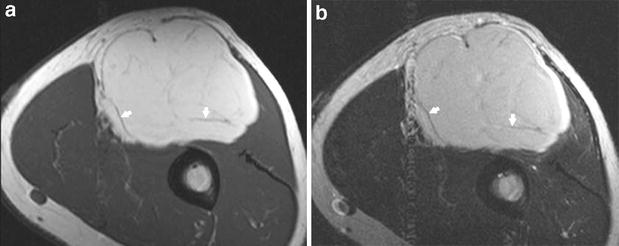

Be sure to check out. They're noncancerous growths of fatty tissue that can develop anywhere on the body. Lipoma (fatty tumor, lipoblastoma, fatty tumor) is a benign neoplasm (tumor) that develops from adipose tissue.

This is a benign formation of fatty subcutaneous tissue.